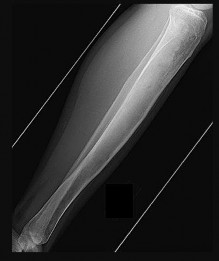

Figures 9a through 9d are the anteroposterior and lateral radiographs, CT scan, and technetium bone scan of a 12-year-old boy who has experienced 7 months of pain in his lower leg. The pain limits his ability to participate in sports and he is having difficulty sleeping. He is afebrile, and laboratory study findings including an erythrocyte sedimentation rate, C-reactive protein, and complete blood count are within normal limits.

The images and clinical history support a diagnosis of osteoid osteoma, which most commonly occurs in adolescence. Although these lesions can be seen in any bone, they are usually located in the femur and tibia. The significant inflammatory response to this tumor is secondary to high levels of prostaglandin production. Characteristic night pain is relieved with nonsteroidal anti-inflammatory drugs (NSAIDs) or by aspirin.

Radiographic images show thickened bone and a small central nidus. Thin-cut CT scan is the imaging of choice to visualize the nidus. A bone scan is associated with uptake but is not specific. Treatment options include expectant management with NSAIDs and observation under the premise that these lesions eventually burn out. Contemporary treatment involves RFA. Historically, these lesions were treated with en bloc resection; however, this technique has largely fallen out of favor because of the high efficacy and comparative low morbidity associated with RFA.

When an osteoid osteoma occurs in the spine, it is located in the posterior elements, and paraspinal pain and scoliosis often are present.